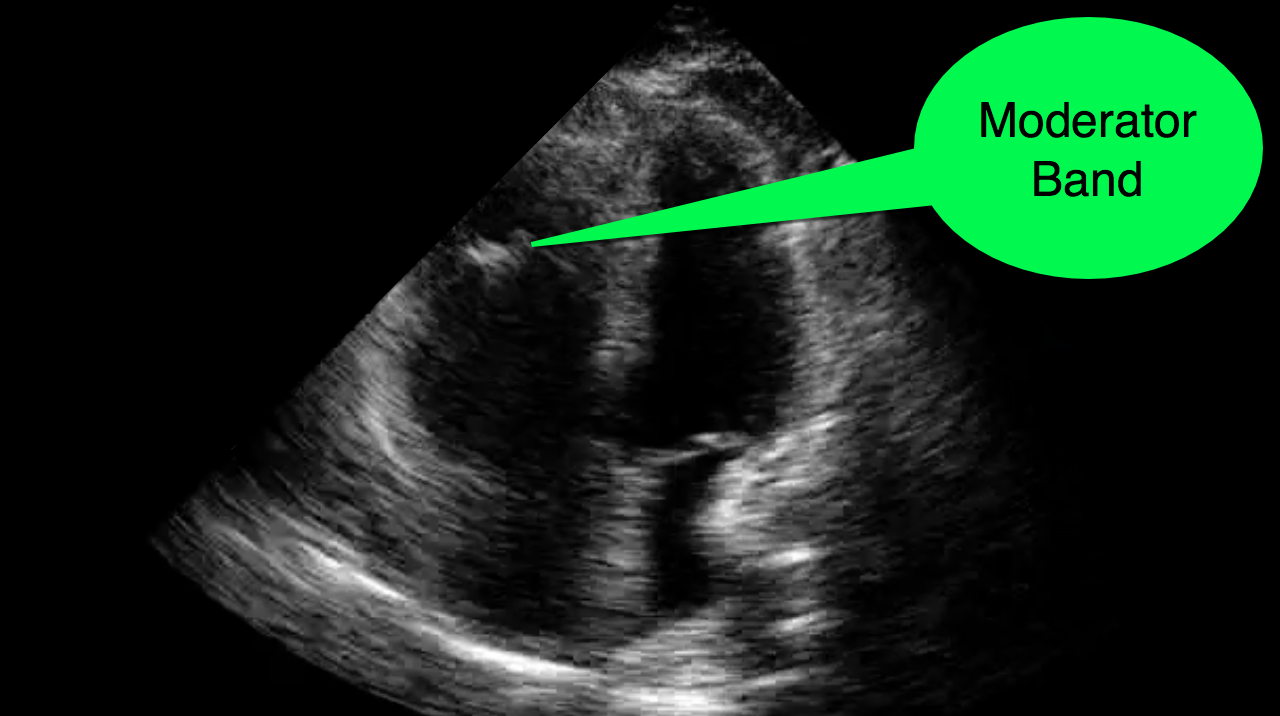

distinguishing characteristics of the morphological rv include uniformly coarse. three prominent muscular bands are present in the rv: The parietal band, the septomarginal band, and the moderator band. normal structures include the crista terminalis, taenia sagittalis, chiari network, coumadin ridge, moderator band, papillary muscles, and chordae tendineae. Aberrant structures include aberrant papillary muscles, accessory chordae, false tendons, and accessory mitral valve tissue. the moderator band in the right ventricle is being increasingly recognised. the moderator band, also called the septomarginal trabecula, is a consistent structure in the morphologic right ventricle and can be helpful as a. the moderator band is located in the right ventricular apex that connects the interventricular septum to the anterior. the moderator band (mb) is an intracavitary structure of the right ventricle composed of muscular fibers.